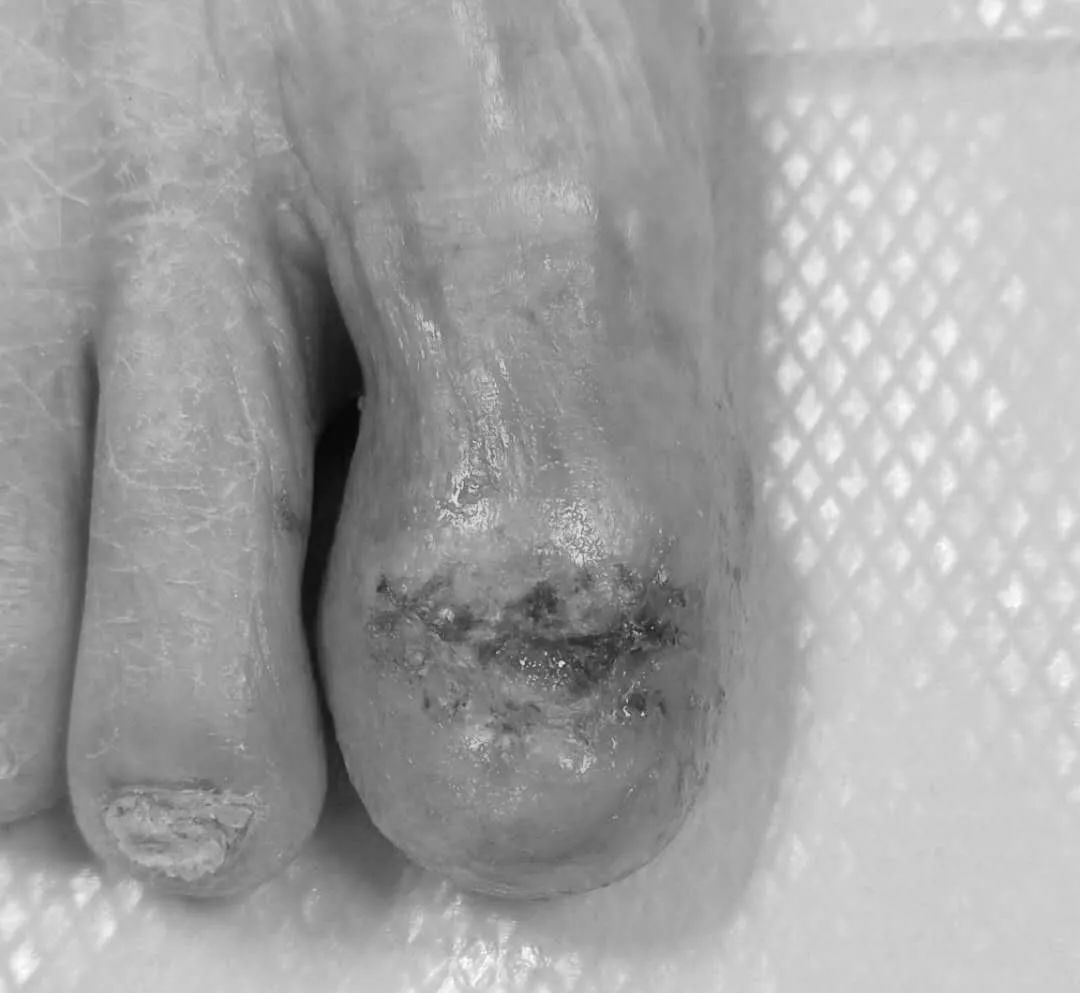

初见阿婆,她被家人搀扶着一瘸一拐地走进诊室,痛苦地伸出了右脚,可见右拇趾甲床表面溃烂,周围肿胀,表面有血痂,并有血性分泌液渗出,压痛明显。

皮肤镜下右大拇趾甲见黄红色背景下片状出血、血痂,中央见鲜红色肉芽性肿物及边缘紫红色结构,这种情况还真不能排除黑素瘤。

最后,根据病史、临床表现、皮肤镜检查及组织病理学检查结果,明确诊断为甲床异物肉芽肿。术后两周拆线,阿婆伤口愈合良好。

拆线后右足第一趾皮损